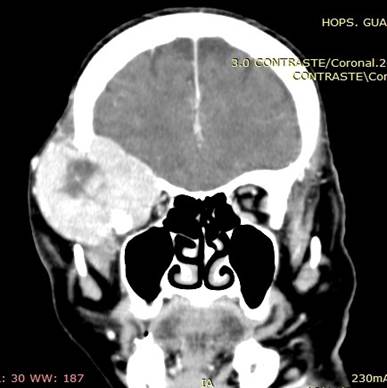

Ilustración 8 Ca de tiroides y metástasis cerebral.

![]() |

Fuente: Hospital de Especialidades Guayaquil “Doctor Abel Gilbert Pontón”.

Autor: Dr. Fernando Moncayo A.

Paciente de 68 años de edad, que ingresa referida de otra institución por presentar más tumoral en región occipital derecha de gran tamaño dura muy adherida, dolorosa con circulación colateral; paciente desorientada en tiempo y espacio, irritable y poco colaborativa, en algunas ocasiones ha presentado convulsiones tónico clónicas. Además, presenta masa cervical voluminosa, a nivel tiroidea, dura, adherida a estructura aéreas y vasculares.

Se toma biopsia con aguja gruesa de lesión tumoral cervical y tumoración occipital encontrando carcinoma papilar variante oncocitica. Paciente fue tratada por el departamento de oncología clínica en forma paliativa y con Sorafenib por no haber mejoría con radio-yodo.